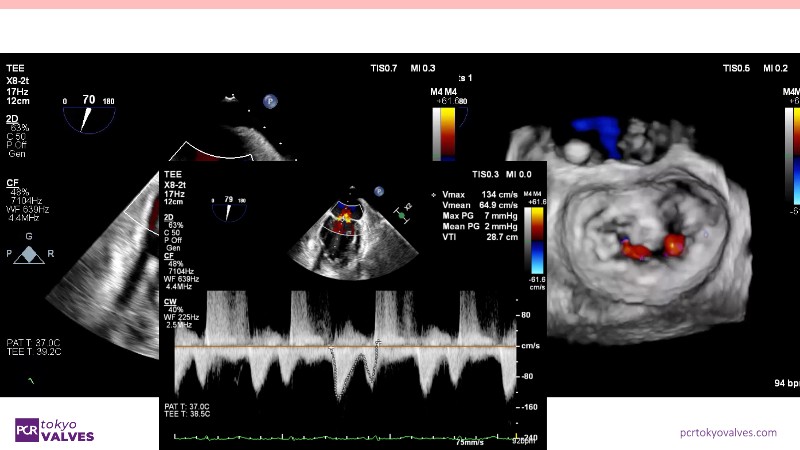

Explore the latest advancements in TEER therapy with this PCR Tokyo Valves 2025 session dedicated to MitraClip. Through expert-led case discussions, gain a deeper understanding of complex scenarios, including restricted posterior leaflet in functional mitral regurgitation, commissure lesion (A3P3), and MitraClip combined with Amulet.